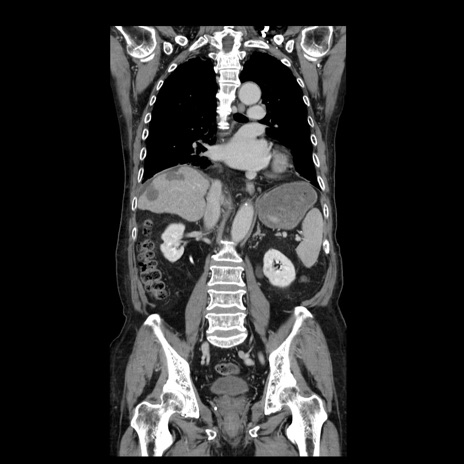

症例21(冠状断像)

【症例】70歳代男性

【主訴】腹痛

【現病歴】肝硬変・肝細胞癌にてかかりつけの方。約9時間前に食後より腹痛出現。症状が徐々に増悪し、嘔吐出現したため来院。

【既往歴】肝硬変、肝細胞癌(RFA、TACE後)

【身体所見】意識清明、表情苦悶様、BT 36℃、BP 129/78mmHg、P 88bpm、SpO2 97%(RA)、右上腹部から心窩部にかけて圧痛あり、反跳痛なし、筋性防御あり。

【データ】WBC 5800、CRP 0.16